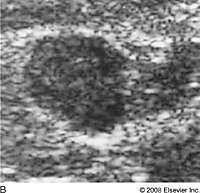

What is Fibroadenoma?

benign breast condition

Estrogen related tumor. Most common benign solid tumor of the breast.

Primarily in young women

What is the Sonographic Appearance of Fibroadenoma?

Oval

Gently lobulated

Hyperechoic

Uniform echogenicity

Smooth distinct borders

Wider than tall

Enhancement

Edge shadowing

Arise from TDLU

Pseudo-encapsulated

What are the presentations of Fibroadenoma?

Painless palpable mass, firm rubbery